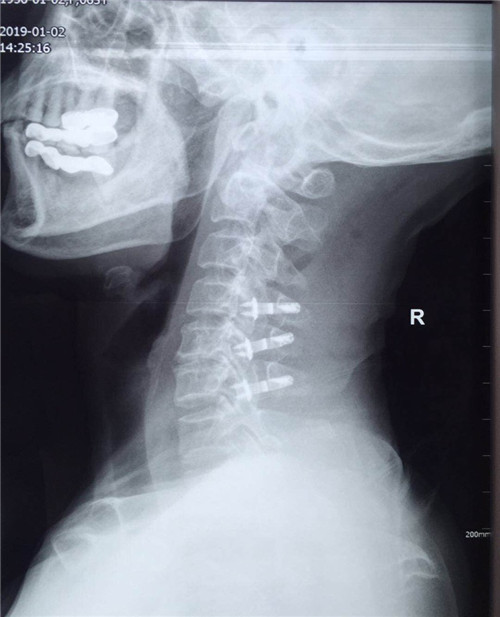

患者入院后,骨一科医护人员为其做进一步检查,诊断为多发颈椎间盘突出并继发颈椎管狭窄症。经讨论研究后,程福宏副主任医师决定为其行颈后路颈4、5、6的单开门椎板扩大成形术,该手术在王小峰主治医师的配合下完成。术中,医生为患者进行彻底的减压脊髓,固定椎板。术后患者恢复较好,症状改善明显,已能够独自行走,恢复正常活动。

术后